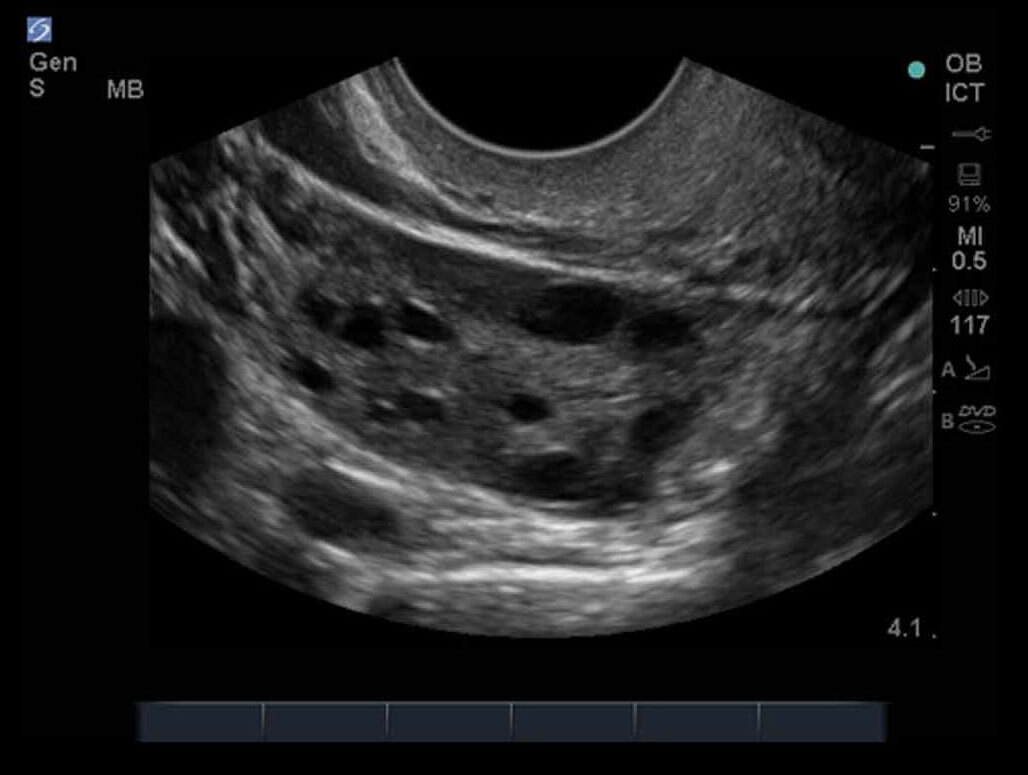

女性の骨盤08画像

M-Turbo:ICT 卵巣2。